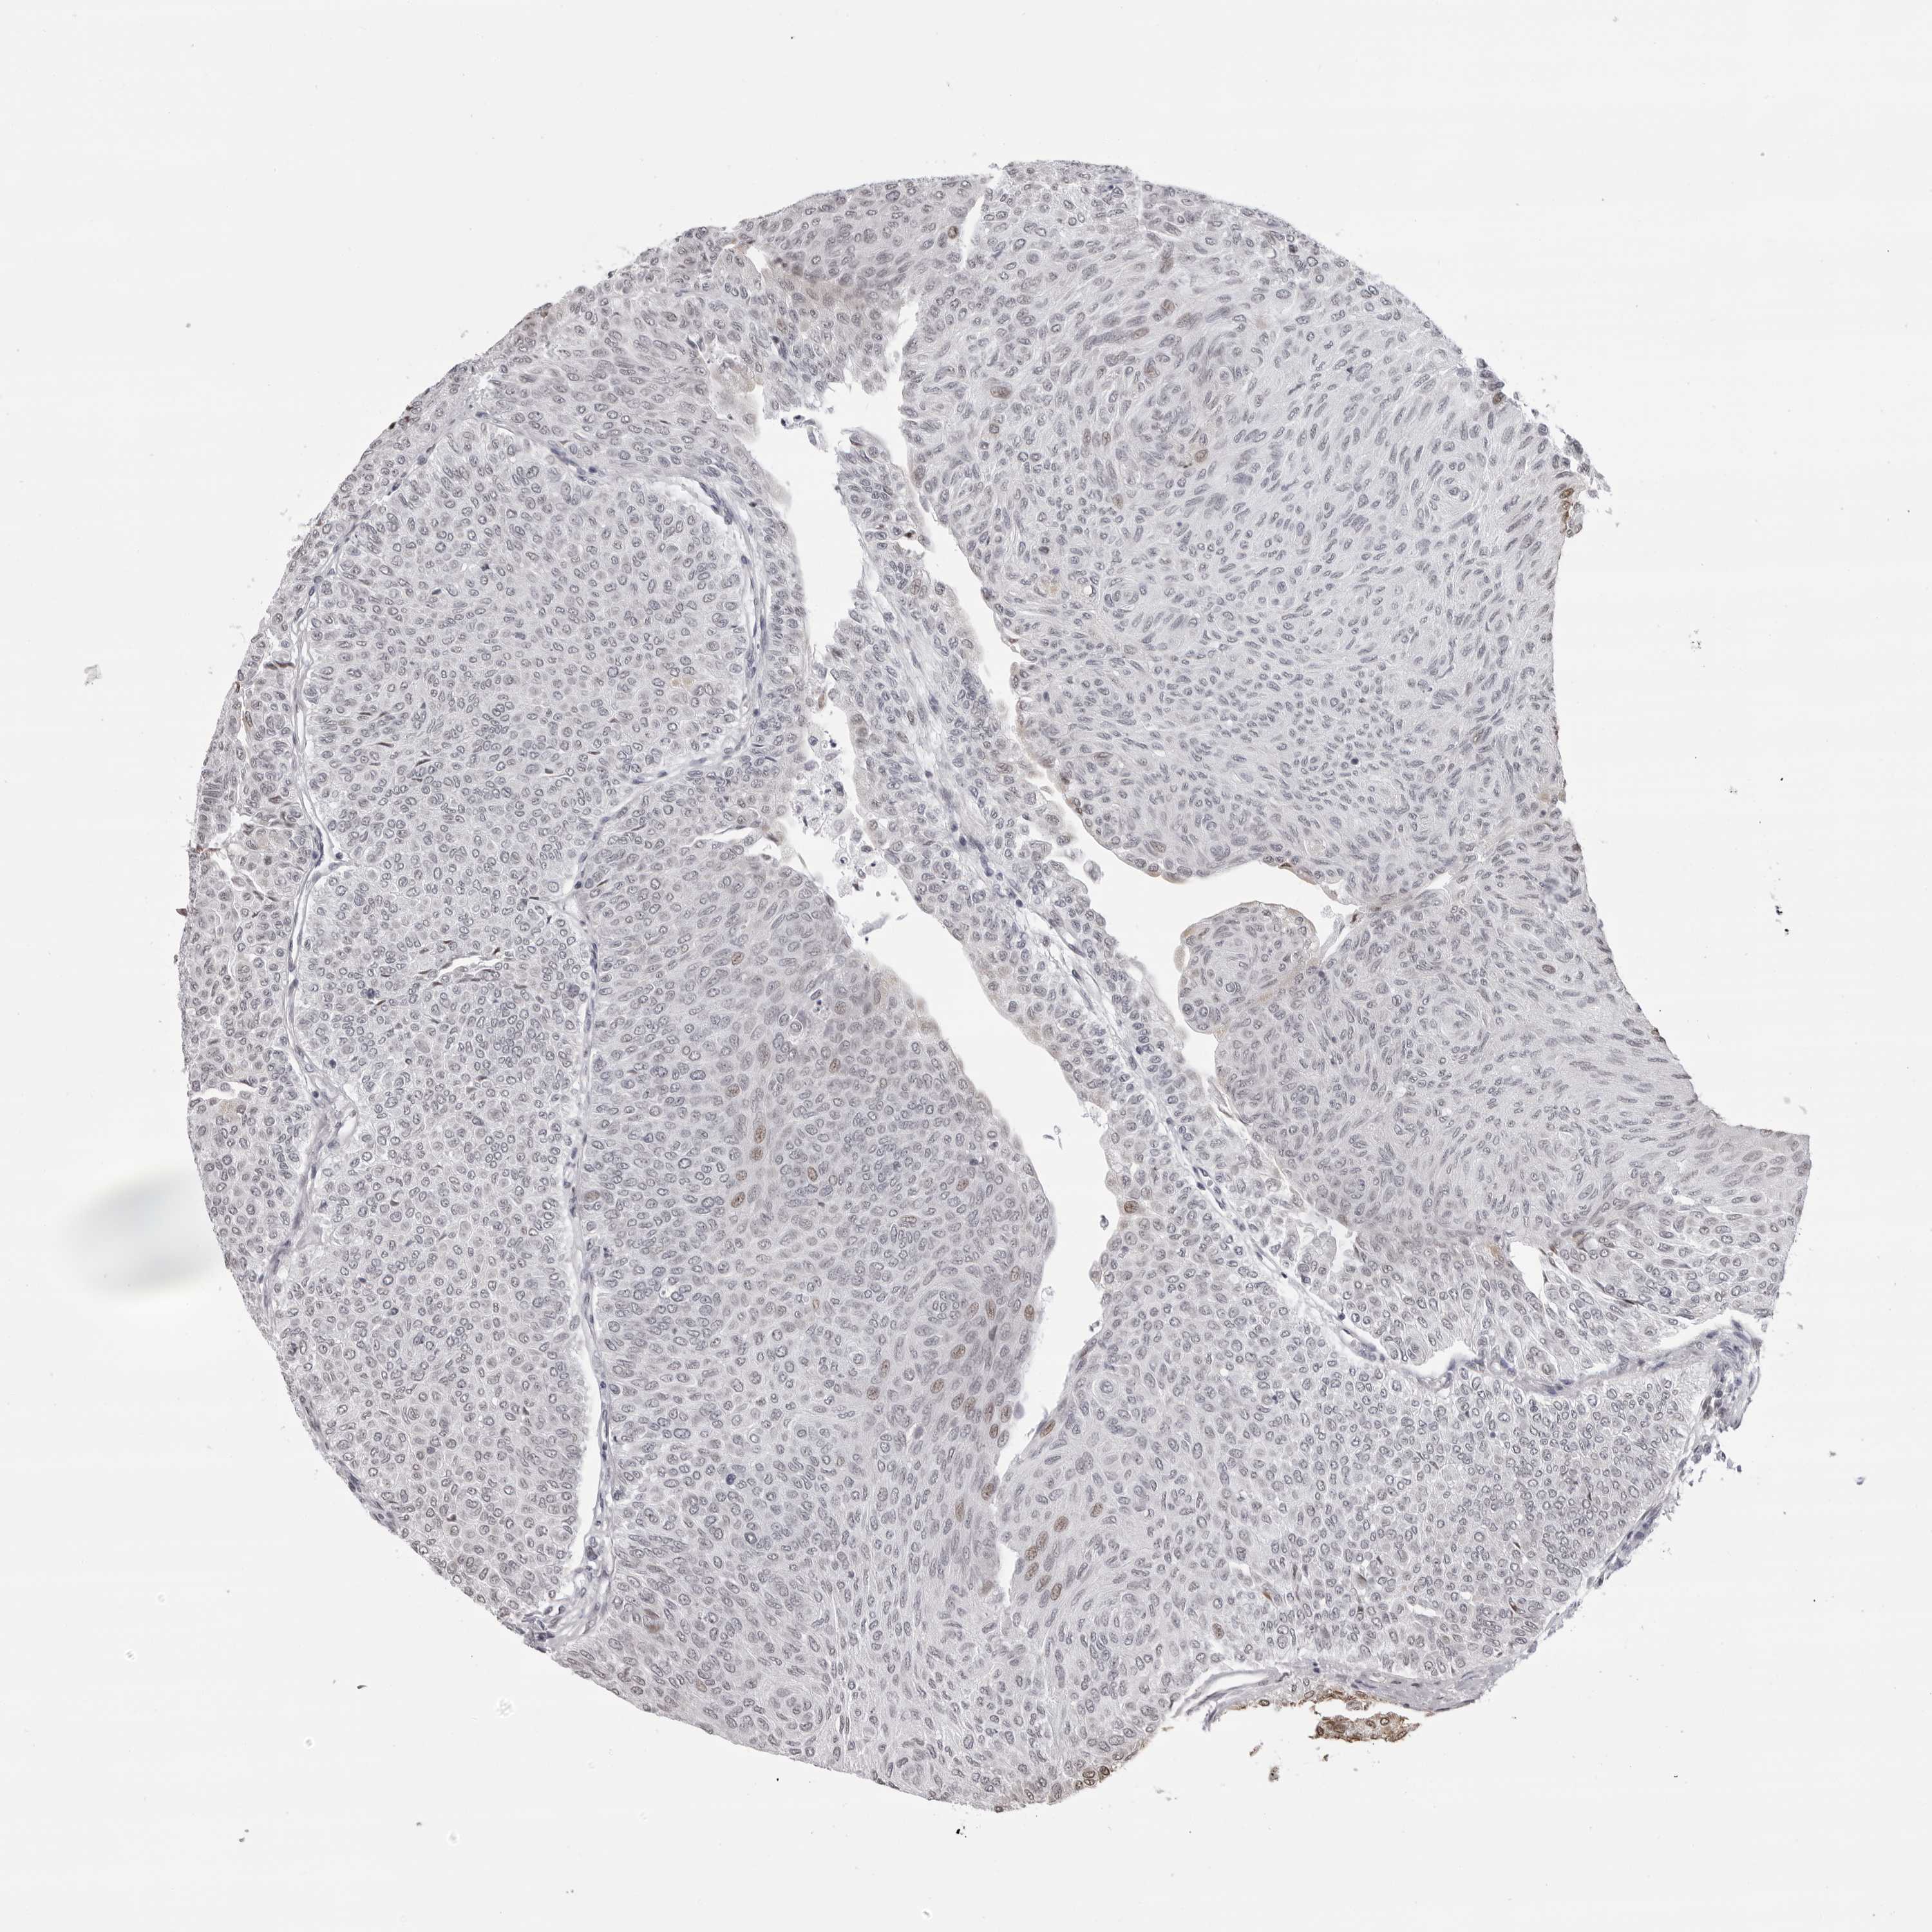

UROTHELIAL CANCER - Protein expressioni

A mouse-over function shows sample information and annotation data. Click on an image to view it in a full screen mode. Samples can be filtered based on level of antibody staining by selecting one or several of the following categories: high, medium, low and not detected. The assay and annotation is described here.

Note that samples used for immunohistochemistry by the Human Protein Atlas do not correspond to samples in the TCGA dataset.

Antibody stainingi

Antibody staining in the annotated cell types in the current human tissue is reported as not detected, low, medium, or high, based on conventional immunohistochemistry profiling in selected tissues. This score is based on the combination of the staining intensity and fraction of stained cells.

Each image is clickable and will lead to virtual microscopy that enables deeper exploration of all samples and also displays staining intensity scores, fraction scores and subcellular localization as well as patient and tissue information for each sample.

Antibody HPA024676

Antibody HPA025763

Staining

High

Medium

Low

Not detected

Intensity

Strong

Moderate

Weak

Negative

Quantity

>75%

75%-25%

<25%

None

Location

Nuclear

Cytoplasmic/membranous

Cytoplasmic/membranous,nuclear

Urothelial carcinoma, Low grade

Urothelial carcinoma, High grade